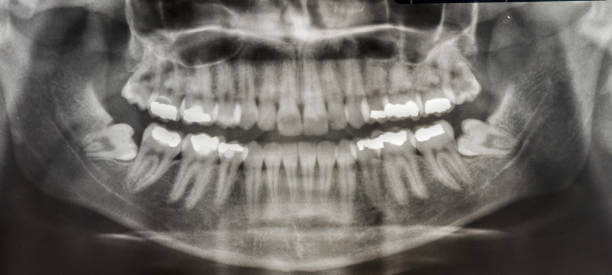

인간은 사랑니를 제외하고 상하 14개의 영구치를 가지고 있습니다. 중앙에 한 쌍의 앞니, 한 쌍의 옆 앞니, 한 쌍의 송곳니, 두 쌍의 작은 어금니, 두 쌍의 어금니가 있습니다. 이 두 어금니보다 작고 큰 어금니 바깥쪽으로 자라는 치아를 '사랑니'라고 합니다. 사랑니의 학명은 '제3대구치'로 세 번째로 큰 어금니를 의미합니다.

사랑니가 다 있게 되면 위턱과 아래턱 양쪽에 하나씩 총 4개가 됩니다. 약 7%의 사람들은 사랑니가 전혀 없으나 만약 가지고 있다면 치아의 수는 사람마다 1~4개로 다양합니다.